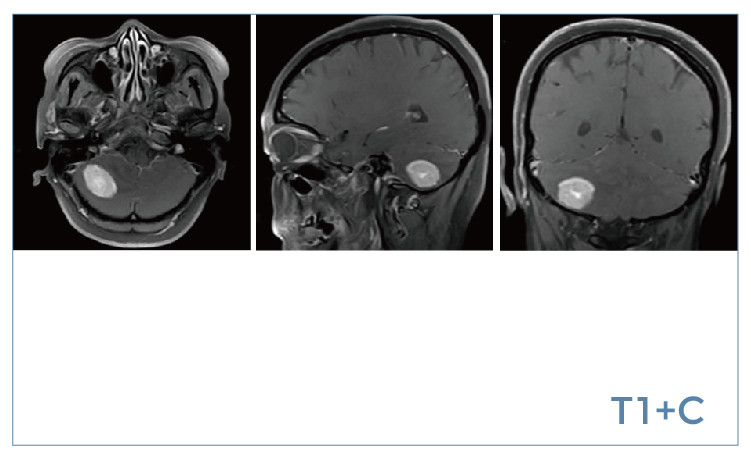

【朗润影像档案】磁共振影像病例分享(编号20190802)